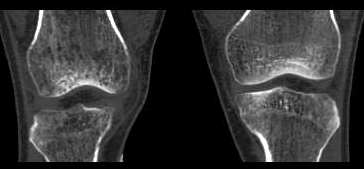

右侧股骨下端 胫骨近端及髌骨见骨质疏松,松质及皮质见虫蚀状溶骨性破坏,皮质变薄,骨小梁减少模糊,胫骨近侧干骺端内侧骨破坏性,关节肿胀,关节间隙增宽,周围未见明显软组织肿块.

就膝关节的病变,我还是支持wawaquan版主的意见,病理上可以解释为长期的关节炎性病变,充血引起的骨质疏松!!多发骨髓瘤好发于扁骨,再说,发生于长骨的多为一骨多病灶,象这样关节两端,骨质改变相同的少见!软组织变化也不支持.

考虑为缺血性改变。股骨远端及胫骨近端均呈同样改变,髓腔及骨皮质均未见骨破坏改变。

无积液,皮质变薄、小梁纤细无中断,骨干变细,周围肌群明显萎缩,不支持mm,也不支持滑膜慢性充血所致骨质疏松,故首先考虑废用性局限性骨质疏松,请结合临床查找疼痛原因。